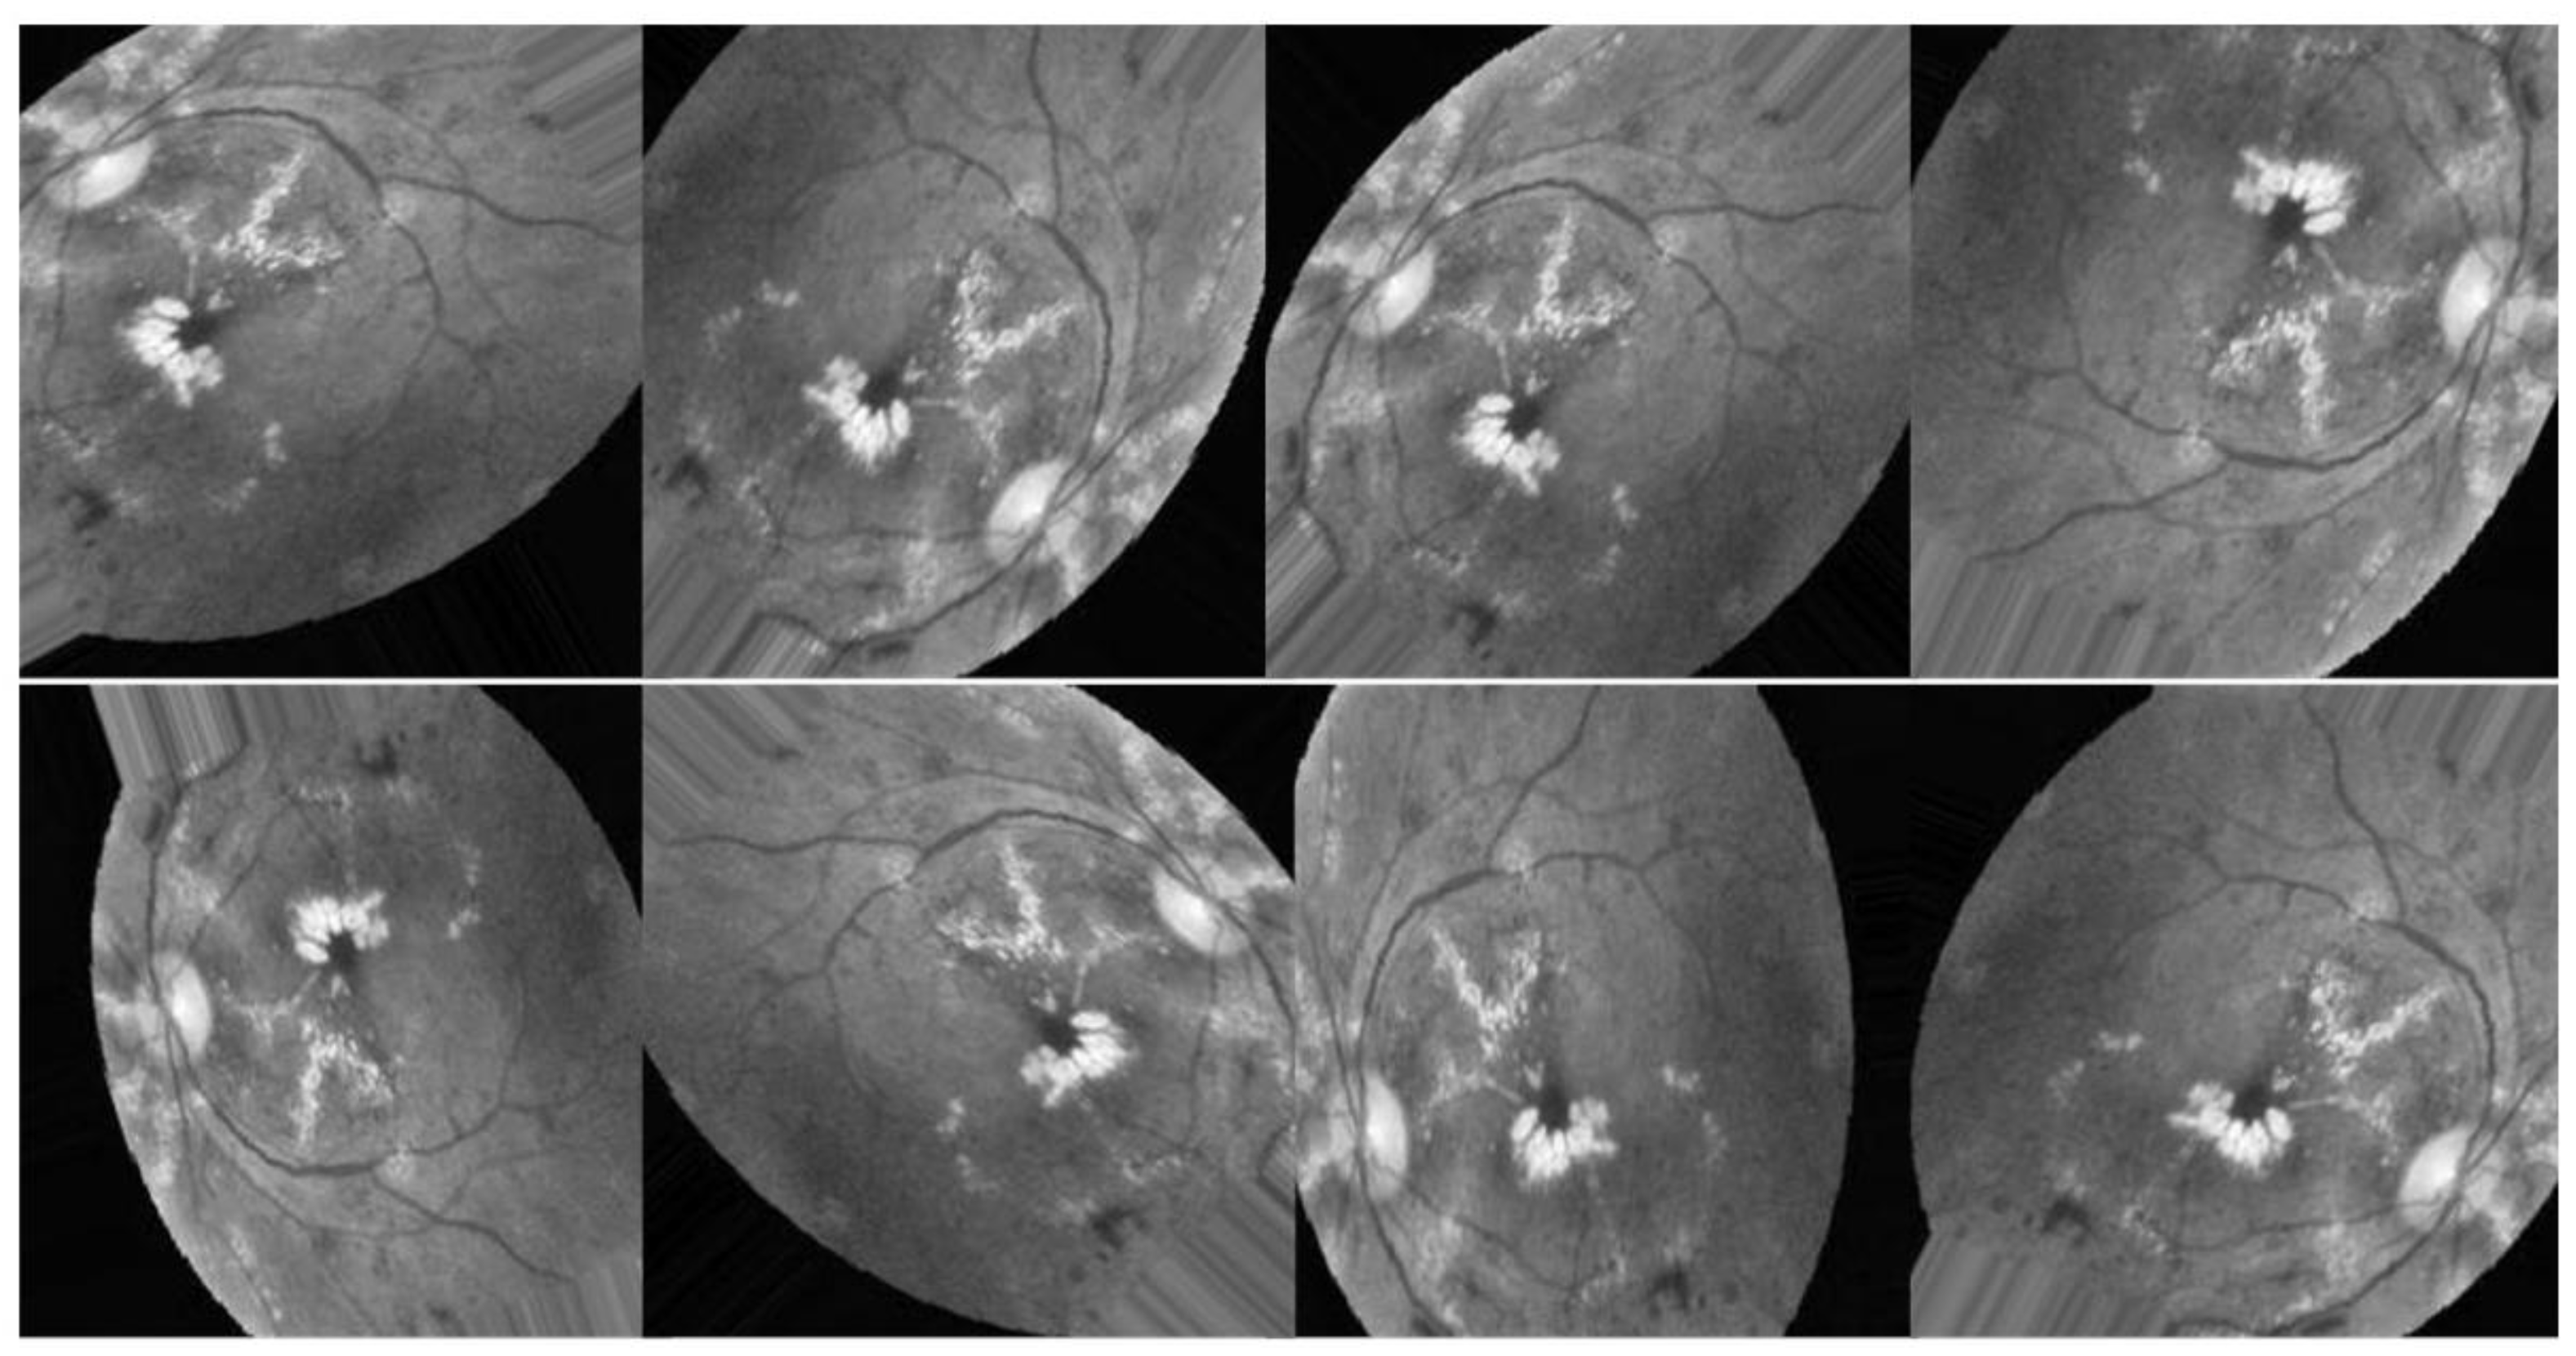

Figure 19 illustrates a sample of photographs belonging to the same class, demonstrating that applying the suggested improvement strategy to the EyePACS dataset provided poor results due to the wide variety of the acquired images and their poor quality. Despite the best improvement approach proposed (CLAHE + ESRGAN), the image quality still fluctuates from one image to the next depending on the nature and resolution of the original image.

Figure 19. Original and enhanced image samples.